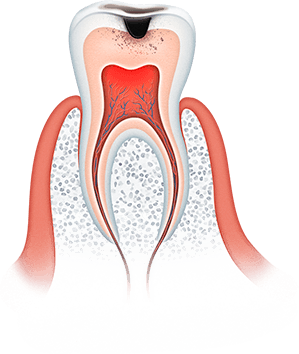

Большинство стоматологических заболеваний необратимые

Важно помнить, что большинство стоматологических заболеваний необратимые, кариозная полость сама по себе не зарастает, костная ткань при пародонтите не восстанавливается, а утраченные зубы не вырастают заново. Болезни полости рта при отсутствии своевременного лечения прогрессируют: кариес превращается в пульпит, пульпит в периодонтит, последний очень часто приводит к потере зуба.